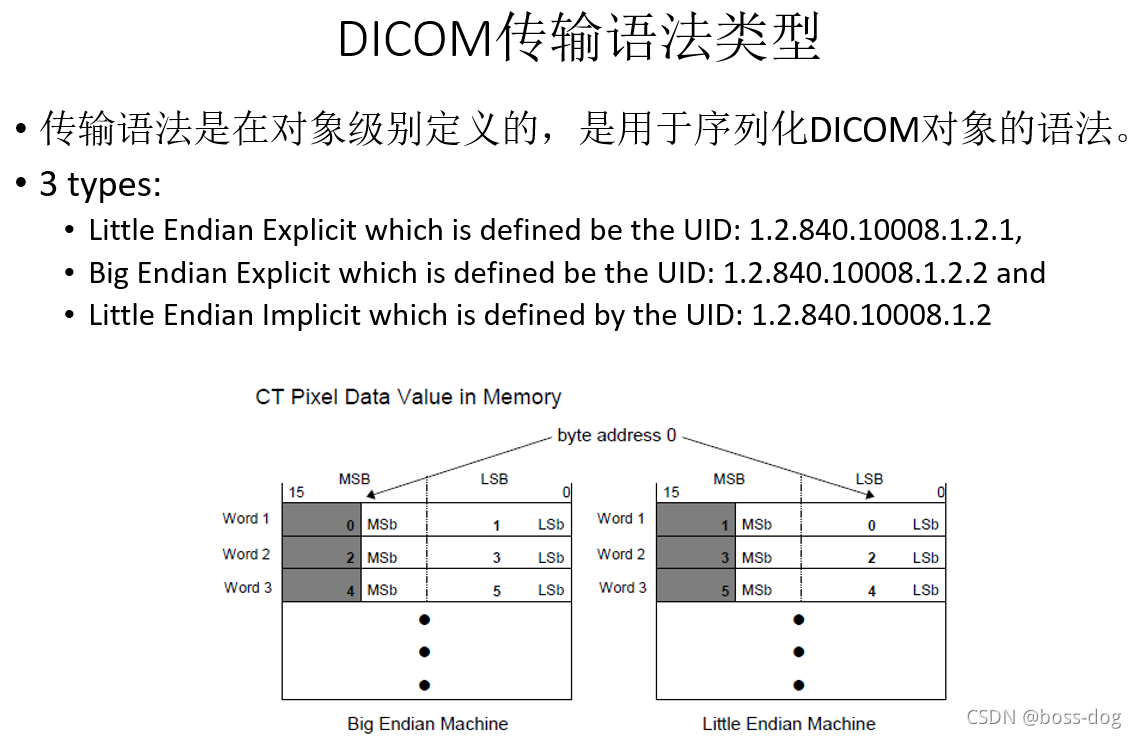

数据集(Data Set)和数据元素(Data Elements)

Tag(地址):譬如0020 0010地址

VR(可选项):可选字段依赖于协商的传输语法

Value Length(值长度):譬如名字给16位、字符给8位,根据值长度确定后面的Value Field(值域)

每一个信息都有一个标签(Tag),且是唯一的;

每个数据字段都有一个唯一的标记或键;

标签是是两个四位的16进制数来组成的,比如(7EF0 0010)就定义为tag标签。